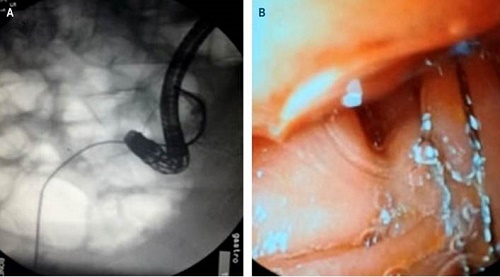

Se decidió, entonces, realizar de forma conjunta la instrumentación de la vía biliar, efectuada por los servicios de cirugía general, a través del tubo en T, y por el servicio de gastroenterología, mediante vía endoscópica. El procedimiento se llevó a cabo en la sala de fluoroscopia, para lo cual se avanzó una canastilla de Dormia y un litotriptor mecánico por el tubo en T. En consecuencia, se logró la fragmentación parcial y el avance de fragmentos al duodeno.

Asimismo, por vía endoscópica, se completó la fragmentación y la extracción de los cálculos, mediante el uso de una canastilla de Dormia (Figura 3) y de un balón extractor. Se realizó una colangiografía por el tubo en T y se observó un adecuado paso del medio de contraste al duodeno, sin extravasaciones de este, y sin evidencia de cálculos residuales (Figura 2B).